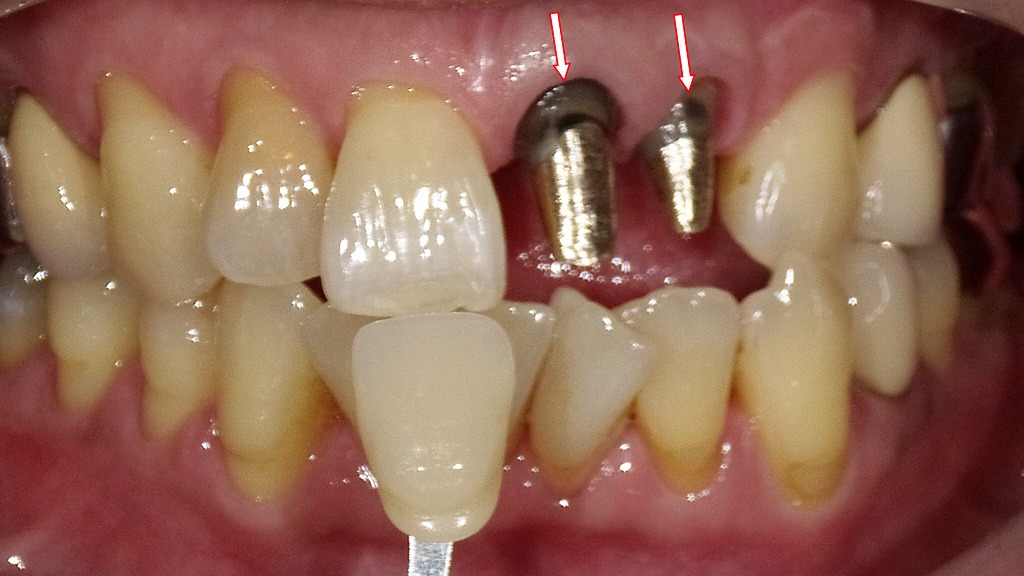

メタルコアによる支台築造とシェードテイキング

この画像は、前歯部の補綴治療中(被せ物作製前)の状態を示しています。赤い矢印で示された部分には、白金加金製のメタルコアが装着されています。以下に詳しく説明します。

🦷 写真の概要

- 赤い矢印の部分:白金加金のメタルコア

- 失活歯(神経を取った歯)の根管内に金属の支台(コア)が入っています。

- この金属は「白金加金」で、強度・適合性に優れ、長期的に安定した材料です。

- メタルコアは歯の根を補強し、その上にクラウン(被せ物)を装着するための土台になります。

- 中央下の歯の前にある白い見本:シェードガイド

- 被せ物の色を決めるための色見本(シェードガイド)を使って、周囲の天然歯と色調を比較しています。

- 自然な仕上がりを得るため、隣の歯の明るさ・透明感・色味に合わせてクラウンの色を選定しています。

- 歯肉の状態

- メタルコア周囲の歯肉はやや退縮し、金属部分が露出しています。

→ これは、過去の根管治療や歯肉退縮によるもので、審美的に気になる場合もあります。

🩺 治療の流れ(この段階の意味)

- 根管治療完了 → メタルコア装着

- 歯の内部の感染を除去した後、金属製のコアで歯の形を補強。

- シェードガイドで色合わせ

- 被せ物(セラミックやジルコニアクラウン)を作製する前に、周囲の歯と自然に調和する色を選定。

- 次のステップ

- 技工所でセラミッククラウンを製作し、最終的に装着して治療完了。

💡 補足解説

- 白金加金コアは耐久性に優れますが、金属色が歯肉や歯の透過光に影響して黒っぽく見えることがあります。

近年は、より審美的な**ファイバーコア(白い支台)**が選ばれることも増えています。